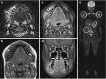

Purpose of review: Chronic non-bacterial osteomyelitis (CNO) with its most severe form chronic recurrent multifocal osteomyelitis (CRMO) is an autoinflammatory bone disorder. We summarize the clinical presentation, diagnostic approaches, most recent advances in understanding the pathophysiology, and available treatment options and outcomes in CNO/CRMO.

Recent findings: Though the exact molecular pathophysiology of CNO/CRMO remains somewhat elusive, it appears likely that variable defects in the TLR4/MAPK/inflammasome signaling cascade result in an imbalance between pro- and anti-inflammatory cytokine expressions in monocytes from CNO/CRMO patients. In this context, we present previously unpublished data on cytokine and chemokine expression in monocytes and tissues. CNO/CRMO is an autoinflammatory bone disorder resulting from imbalanced cytokine expression from innate immune cells. Though the exact molecular pathophysiology remains unclear, variable molecular defects appear to result in inflammasome activation and pro-inflammatory cytokine expression in monocytes from CNO/CRMO patients. Recent advances suggest signaling pathways and single molecules as biomarkers for CNO/CRMO as well as future treatment targets.